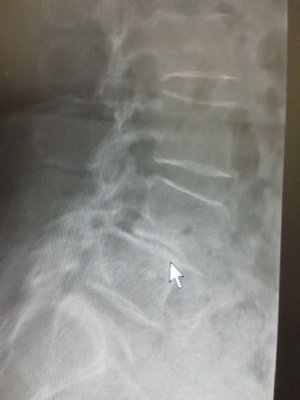

• 腰痛分離・すべり症

腰痛すべり症とは椎骨が前方にずれた状態で腰痛すべり症と腰椎分離すべり症がある。

主な症状は坐骨神経痛や間欠性跛行である。